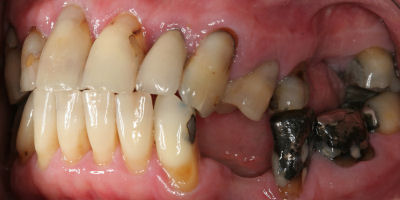

Before/After